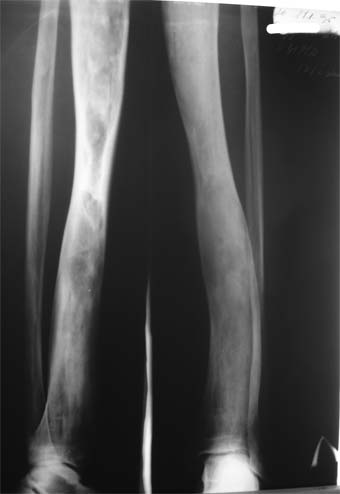

Коллеги! Пациент Д., 35 лет, В 1985 году был поставлен диагноз гемигипоплазия правой нижней конечности. Укорочение 5 см, в 1987 году остеотомия правого бедра, аппарат 4 месяца, удлинили на 2 см из-за нагноения спиц аппарат сняли.

Эти жалобы беспокоят втечение 5-6 лет. В 1999 году выявили "изменения" (со слов больного, выписки нет на руках) бедренной кости и костей голени слева. Тогда же предложили в ЦИТО срочно делать какую-то операцию.

Левая нижняя конечность. Левое бедро увеличено в объеме, при пальпации пальпируется бедренная кость большего диаметра по сравнению с левым бедром. Пальпация безболезненна.

Голень обычной формы. Объем движений в суставах полный. Кровоснабжение, иннервация сохранены. Имеется разница в длине конечностей правая короче на 4-5 см за счет бедра и голени.

В приложении вид больного и рентгенограммы бедра 2001 год и 2005 год.

2001

Что бы это могло быть? О чем можно думать? Онкология?